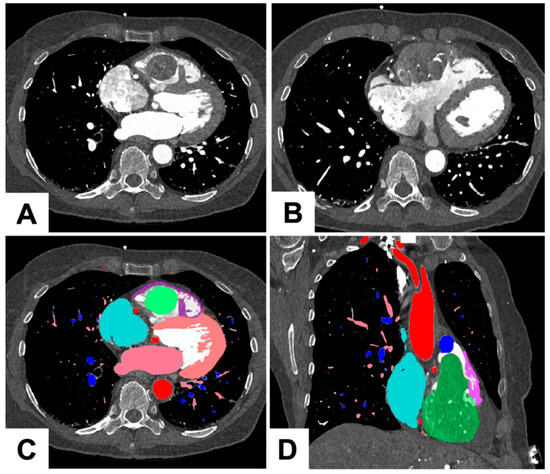

1.2. Three Dimensional Printing Process for the Tumor

As shown in Figure 2 and Figure 3, the 3D printing process for the tumor had several sequential steps. After the imaging process, the 0.2 mm slices were imported into Mimics 24.0 (Materialise, Leuven, Belgium). The segmentation of different anatomical structures was executed through a combination of thresholding and manual segmentation techniques. The segmented structures encompassed the aorta and coronary arteries, blood pools of both the left and right atrium, myocardium of the left and right ventricles, aorta, pulmonary veins, pulmonary arteries, and the tumor itself. The manual segmentation process was a collaborative effort involving an experienced radiologist and a cardiac radiologist working together to ensure accuracy and precision in identifying and delineating these structures.

Figure 2.

Illustration of preoperative 3D tumor excision planning. (A) Axial slice: Image illustrating the tumor’s pedunculated section as it approaches the RVOT; (B) Axial slice: Slice demonstrating tumor extending through the myocardium of the RV; (C) Color-coded visualization: The tumor mass is indicated in green, the right ventricle in purple, the LV in peach, the RA in cyan, the left atrium and pulmonary veins in pink, the pulmonary arteries in blue and the aorta in red; (D) Coronal section: The view along the tricuspid plane, displaying the tumor’s pedunculation extending through the RVOT.